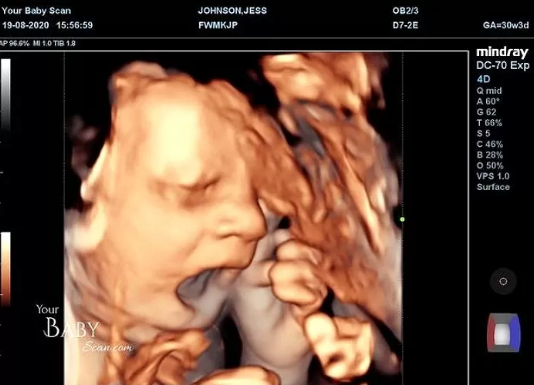

それはイギリスでの出来事。こちらの夫婦に第1子を授かったとのことですが、最近になり夫婦が妊娠30週目のエコー写真を公開しました。そこには胎児の姿がはっきり見えるのですが、胎児が一見変わった仕草を見せているとのこと。なんと、胎児が中指を立てる姿が映し出されていました。

まだ、指が完全に形成されてはいないものの、中指を立てているのが一目瞭然。もしかするとエコー写真を撮られているのに気づいており「早く終わらせろよ…」とアピールしているのかもしれません。これには夫婦も目を疑ってしまいました。

さらに、顔からも不満げな姿が映し出されており、胎児が思いっきりあくびをしています。その後、身体を隠し始めたというので、もしかすると「恥ずかしいからこれ以上見ないでくれ」という意思表示なのかもしれませんが、両親は意外にも好意的。性別は男の子ということですが、「早く生意気な我が子に会いたい」とのこと。